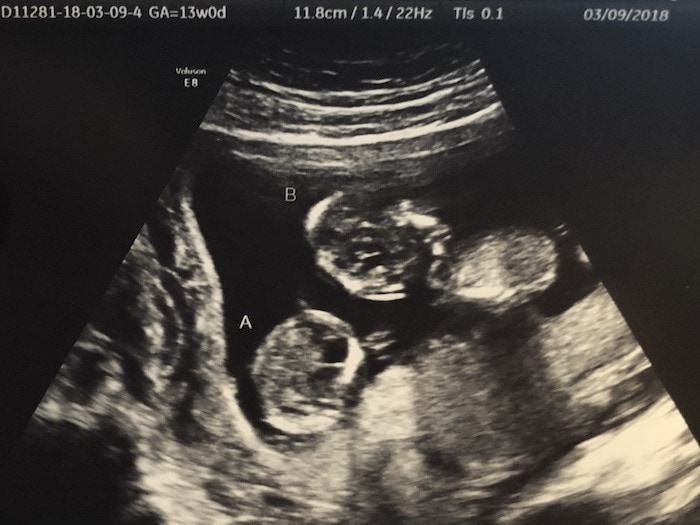

- Ultrasound Photos at 13 Weeks Pregnant With Twin

Ultrasound Photos at 13 Weeks Pregnant With Twin